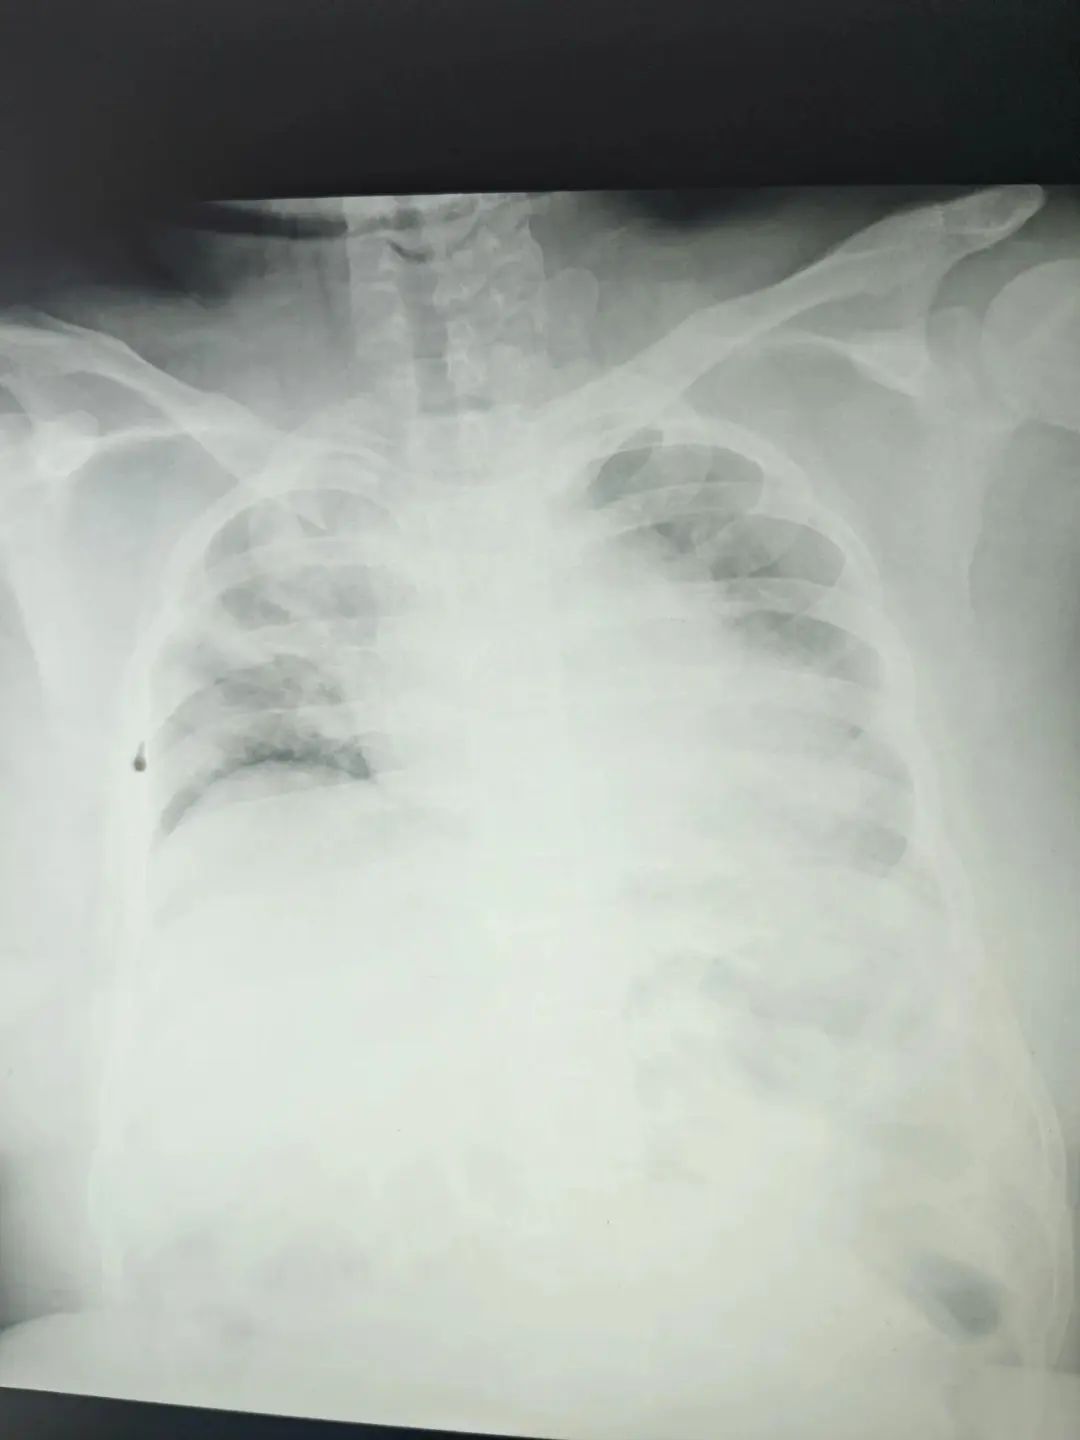

双肺白化,高烧惊厥危重病人

当患者因昏迷一天被送往医疗队所在的医院时,他们已经处于极其危险的状态:胸片显示双肺大规模“白肺”,血氧饱和度降至80%,体温飙升至39℃,并伴有反复抽搐。沙温分队成员、瑞金医院卢湾分院重症医学科主治医师汪矛斐面对智力低下无法沟通和配合治疗的特殊情况,以及当地上级医院没有床位的困境,毅然承担起治疗的重任。他说:“面对生活,我们无路可退”。